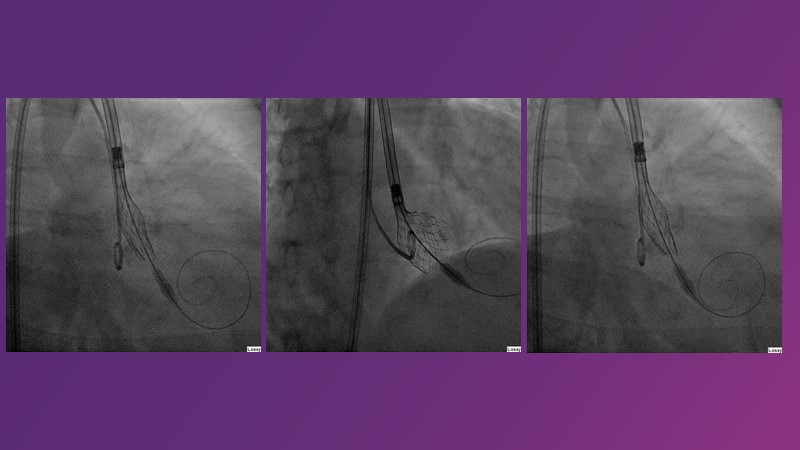

This session reflects on the importance of device choice and implantation technique in complex TAVI procedures. Learn how to anticipate the risks of a valve-in-valve procedure in small surgical prostheses, and discover the latest technological evolutions for treating patients with complex anatomy.

- To appreciate the importance of device choice and implantation technique in complex TAVI procedures